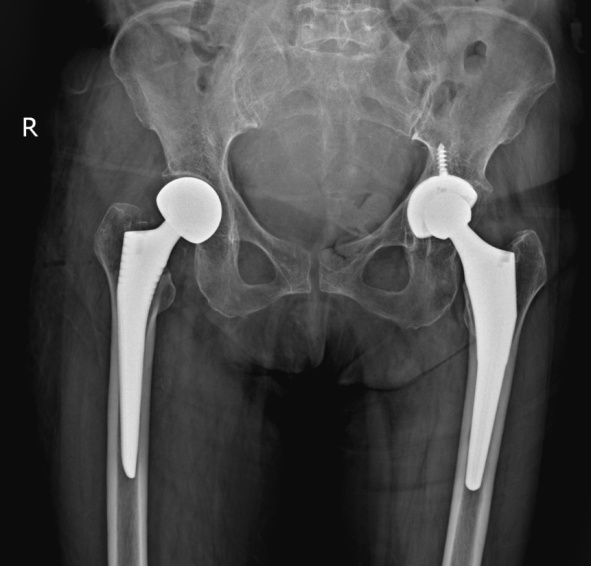

前来就诊时,徐奶奶的家人回忆,老人活动时不慎摔倒,右边髋部着地,当时她感觉髋部有剧烈疼痛,不能活动。在家中休息一段时间后,疼痛迟迟无法缓解,于是来到方塔中医医院骨伤科就诊。接诊医师经过仔细问诊、查体及影像学检查后,诊断徐奶奶为右股骨颈骨折,且断端错位。

为此,团队想到了人工髋关节置换。其中,人工股骨头置换(半髋)较人工全髋关节置换手术时间更短,出血量更少,手术可以在麻醉医师团队的配合下进行局部麻醉,可以降低高龄患者的麻醉风险和手术意外,具有一定优势。此外,相较于股骨颈骨折空心钉内固定,术后患者不能下地负重行走,人工髋关节置换的患者则可以在术后早期、疼痛耐受的情况下进行地面活动,对于高龄患者是更优的手术方案,具有快速康复,减少术后并发症等优点。经过严密的讨论,手术团队最终制定了人工股骨头置换(半髋)的手术方案。

骨伤科团队与患者及其家属充分沟通病情,患者和家属同意接受手术治疗。手术团队仅用不到一个小时,顺利进行了右侧人工股骨头置换(半髋)术。目前,徐奶奶已康复出院。而在出院前,她已能够在助行器的辅助下进行走路练习,避免了骨折后因长期卧床引起的一系列并发症,对于改善创伤后的生活质量有很大帮助。